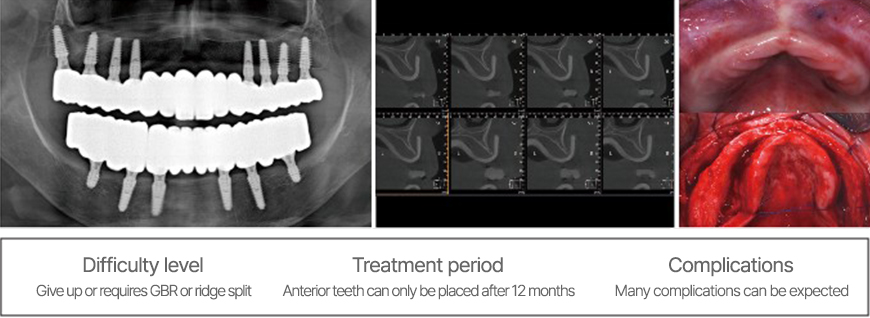

Como tratar estes casos?

É possível colocar implantes numa crista anterior atrófica e fina?

Neste caso difícil, normalmente é criada uma área de póntico longa na região anterior.

Caso muito grave de periodontite, com defeito ósseo extenso, sem cortical labial e perda óssea vertical. Será possível colocar implantes?

Os implantes foram colocados após regeneração, mas ocorreu recessão 10 anos depois devido à reabsorção da crista após a extração. Existem muitos casos semelhantes.